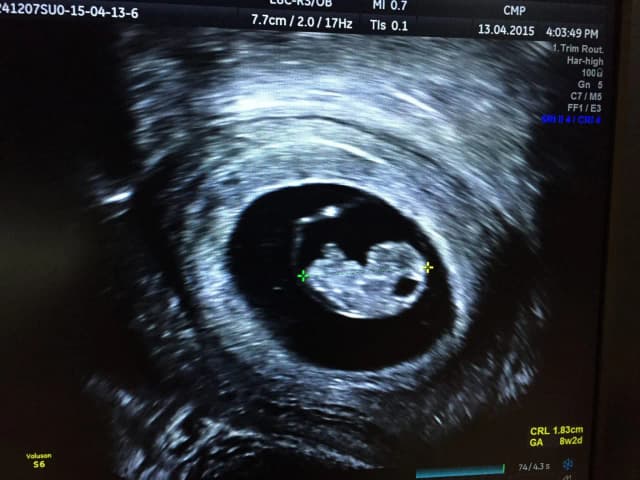

Po jakim czasie widać ciążę? Pierwsze oznaki i metody wykrywania

Dowiedz się, po jakim czasie widać ciążę i jakie są jej pierwsze oznaki. Poznaj skuteczne metody wykrywania ciąży, od testów domowych po USG. Sprawdź, kiedy zrobić test ciążowy.